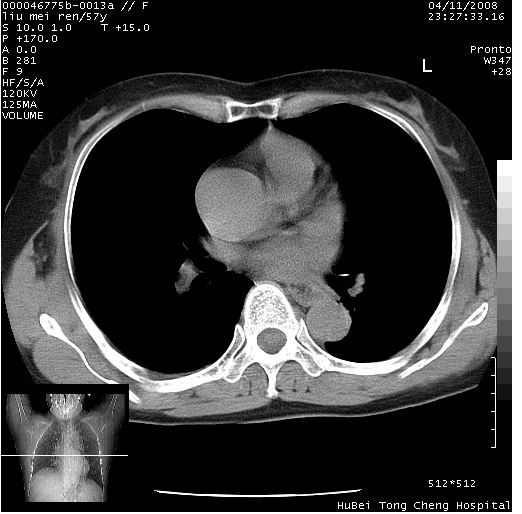

患者 女,57岁。因车祸受伤,其家属要求行“全身ct检查”。平素健康。

胸部ct轴位平扫(层厚10mm,螺距1.5,重建间隔10mm),图像如下:

左位上腔静脉,先天变异。

左位上腔静脉,先天变异。与双侧上腔静脉区别。